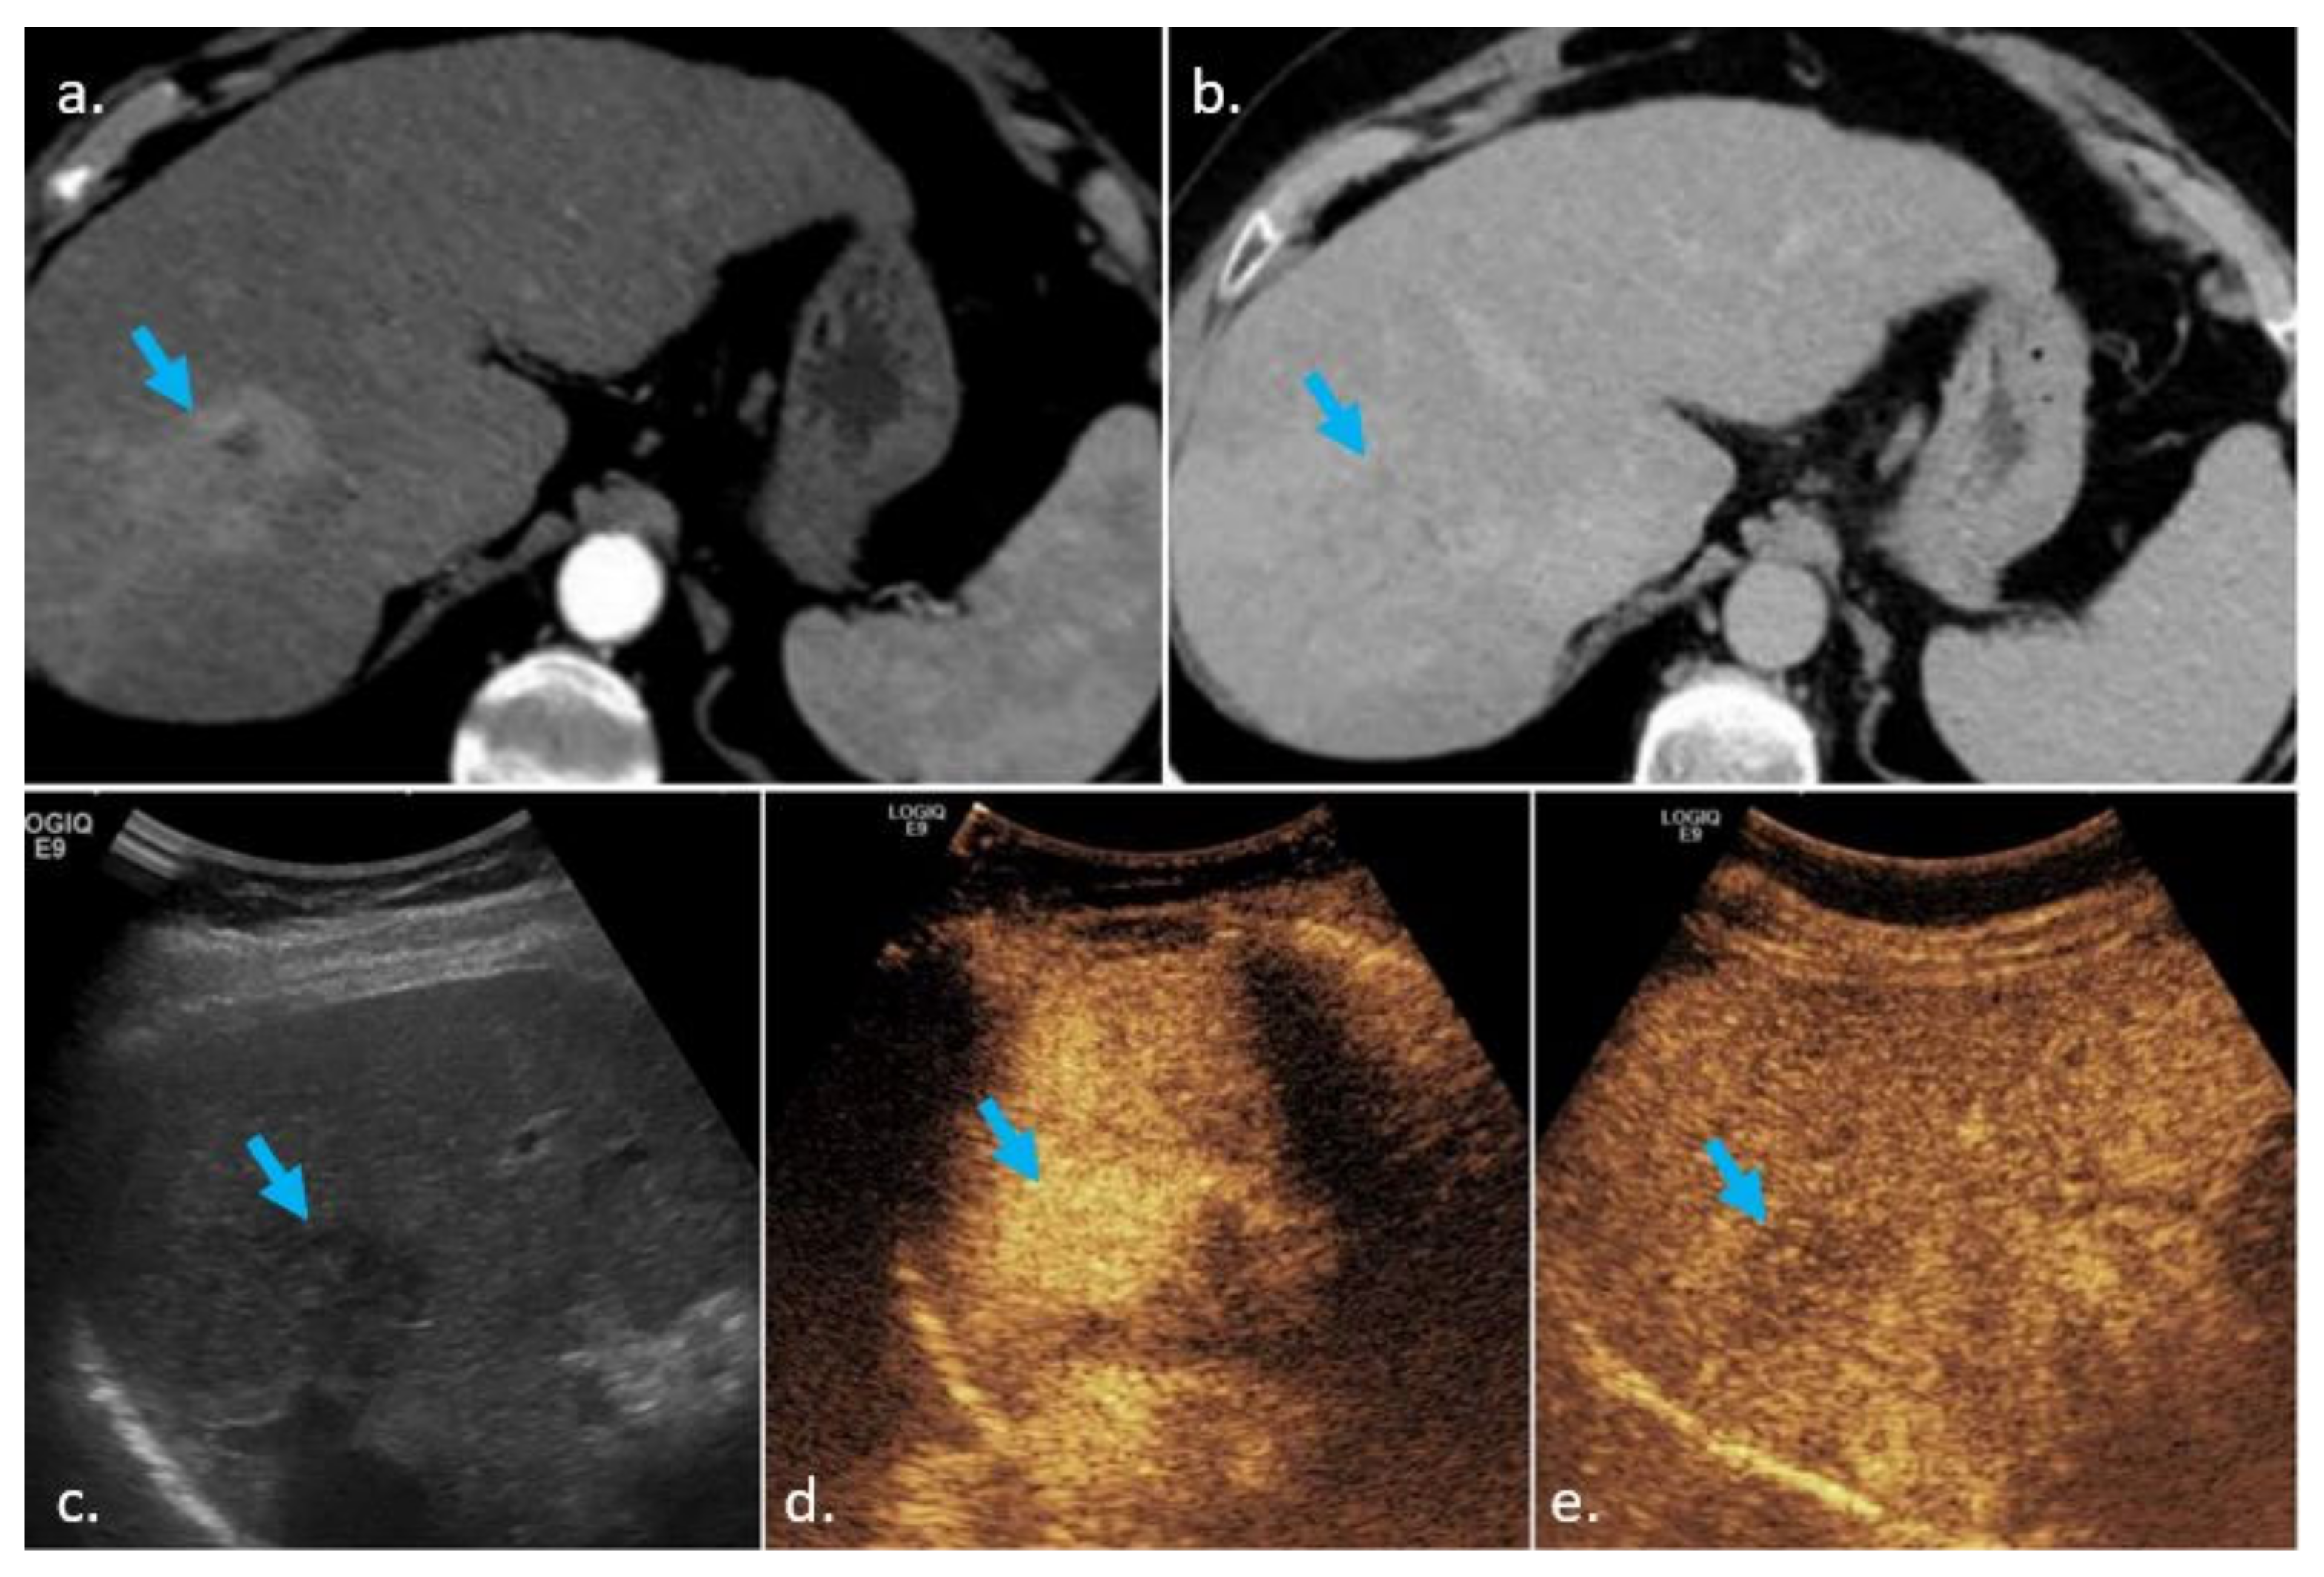

3.2. Washout

3.2.1. Definition

3.2.2. Comparison of CEUS, CECT and MRI, Similarities and Differences

Similarities

Differences and Complementarity of Techniques

- Washout versus “washout”

- The characterization of washout by its onset and degree

- The characterization of washout by its spatial pattern

- CEUS is more sensitive than CT/MRI for depicting washout. In nodules with APHE but without washout on CT and MRI (LI-RADS 3 or 4), CEUS can prove the presence of washout, upgrading the nodule to LI-RADS 5 and, by this, avoiding biopsy. We recommend CEUS in nodules with APHE, but without washout on CT/MRI. On the contrary, if the observation, presenting only with APHE on CT/MRI, is not seen on US/CEUS, it is more likely a vascular pseudolesion and can be confidently considered as benign.